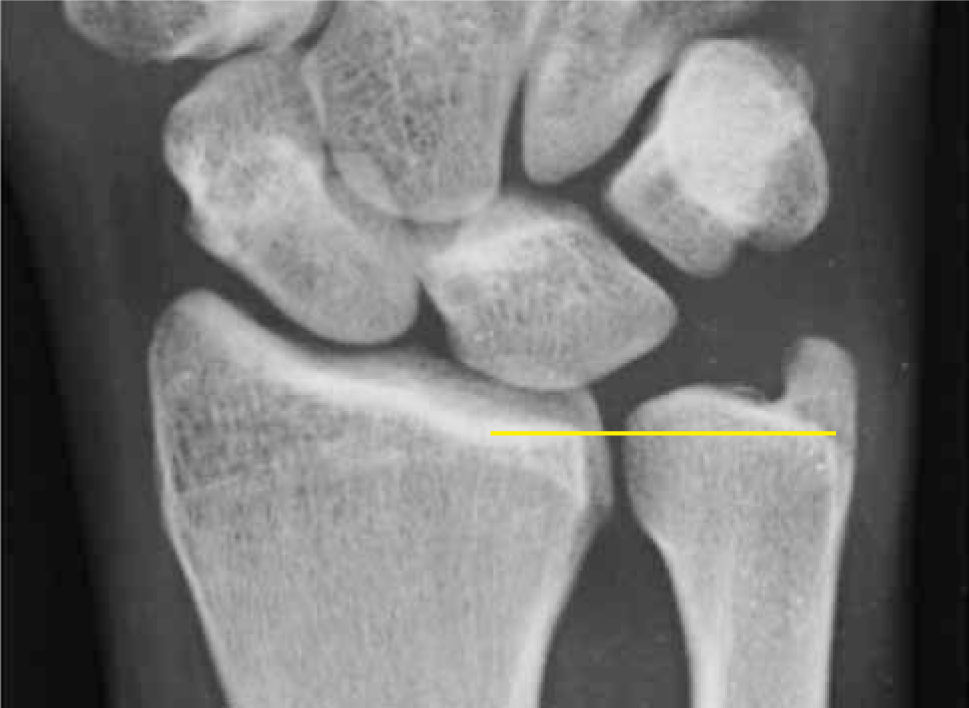

La varianza cubital debe ser medida, es importante destacar que cambia significativamente con la rotación de la muñeca, en pronación la varianza cubital sube y decrece en supinación (13).

Una evaluación radiográfica dinámica al hacer realizar un puño en pronación y con fuerza, mostrara la máxima varianza cubital positiva. Esto en el escenario de estar pensando en un síndrome de impactación cubital dinámico, que ocurre debido a un alargamiento relativo del cubito con la maniobra de pronación y flexión de los dedos forzada.

Los hallazgos encontrados en la radiología simple usualmente muestran una varianza cubital positiva. Si la varianza es normal, y persiste la sospecha clínica, es posible realizar una radiografía dinámica con la muñeca pronada y realizando un puño, esto puede mostrar un relativo alargamiento del cúbito de hasta 2-3mm.